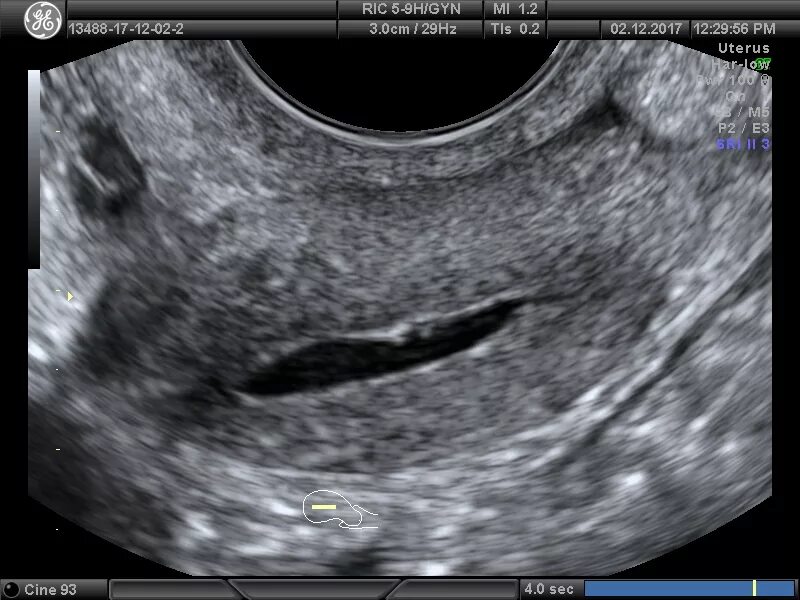

Гематометра симптомы